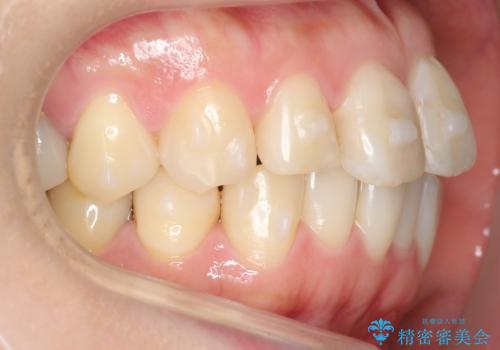

ご希望のマウスピース矯正で歯並びが綺麗になり、大変喜んで頂けました。

食事の度のマウスピース着脱や歯を磨いてからの装着がお仕事上大変なようでしたが、

「1ヶ月程度で慣れましたし、間食の回数が減り歯並びも整って一石二鳥です!」

と治療途中に明るくおっしゃっていました。

治療後には笑うと見えて気になっていた銀歯も白くなり、より一層素敵な笑顔を見せて下さいました。

ホワイトニング予定のため、セラミッククラウンの色は隣在歯よりやや白めにオーダーしました。

左下7欠損に関してはインプラントを検討中とのことです。